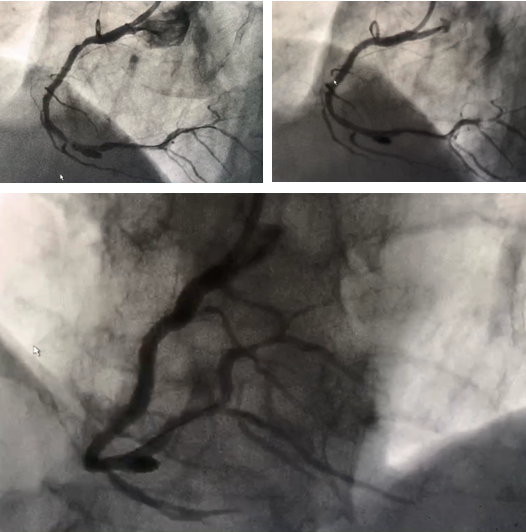

此次实施冠状动脉瘤介入封堵术的病人为一70岁老年男性,因“头昏2月,加重伴胸闷1周”到老年病科就诊,患者11年前曾因冠心病在我院实施冠状动脉介入手术,于右冠状动脉近端及远端植入支架治疗,入院后于2018年5月24日行冠状动脉造影检查发现患者原右冠状动脉近端及远端支架内无异常,中远端可见重度狭窄,狭窄后可见直径约7mm动脉瘤,由于瘤体较大,存在随时破裂导致患者出现猝死的风险,因此必须进行处理,目前常用的技术中普通心脏支架无法封住较大瘤体,而在瘤体部位植入带膜支架虽可以封住瘤体,但是带膜支架再狭窄发生率高,不利于患者预后,经过慎重考虑并与患者沟通交流同意后,李兴升主任决定联合多学科择期为患者实施冠状动脉瘤体介入封堵术。

经过细致的准备,2018年5月28日,李兴升主任在神经外科陈维福教授和放射科杨伟技师的协助下,为患者成功实施了冠状动脉瘤介入封堵术,李主任首先处理了患者右冠状动脉狭窄,通过球囊扩张后植入支架,然后在陈维福教授帮助下成功将弹簧圈释放进入冠状动脉瘤体内,造影显示右冠状动脉远端狭窄解除,冠状动脉瘤体成功封堵,介入室响起了热烈的掌声,这掌声不仅是对我科成功完成重庆地区首例冠状动脉瘤介入封堵术的鼓励,更是对神经外科及放射科支持的感激,还饱含着对手术成功后患者转为为安的喜悦之情!